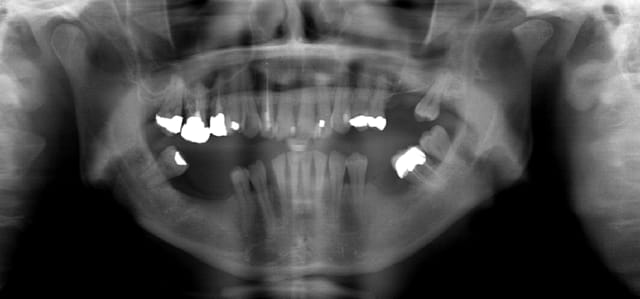

vite fait quelques copies d'écran de la Gendex CB 500 acquise il y a un an (avec le capteur de 1 ere génération)

Les modèles vendus actuellement ont un capteur optimisé pour les panos

Exemple pano 4 vyftad - Eugenol

Exemple pano 1 xdhhsl - Eugenol

Exemple pano 2 nvjrd6 - Eugenol

Exemple pano 3 g3nfut - Eugenol